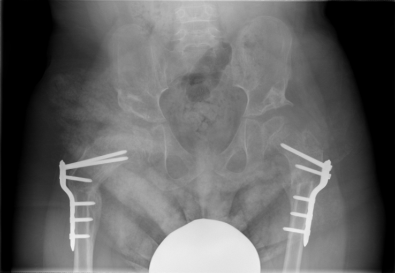

This child had bilateral hip surgery and soft tissue releases by Dr Zenios in one surgery